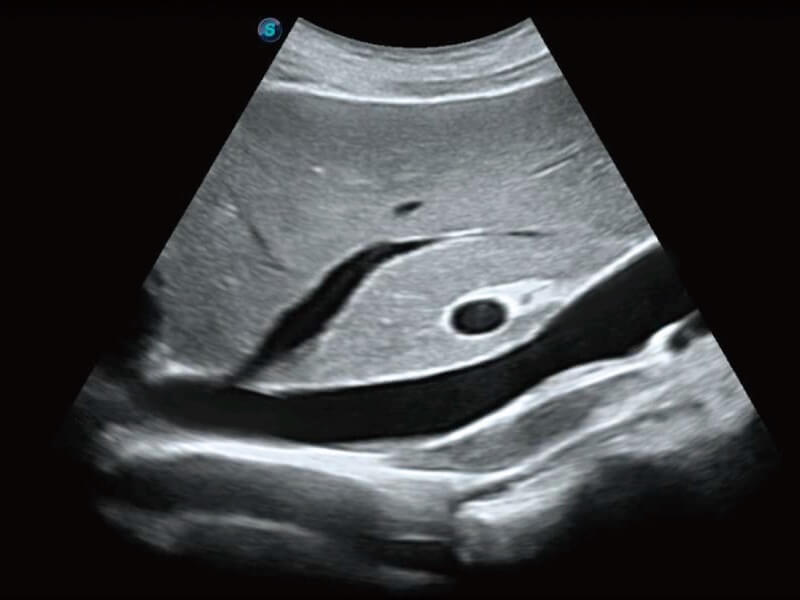

Auto NT ermöglicht halbautomatische, standardisierte Messungen der Nackentransparenzdicke in 2D-Bildern und verringert die Abhängigkeit des Anwenders von den Ergebnissen.